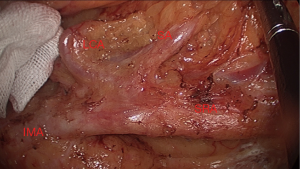

At the same time, we should dissect the lymph nodes along IMA, vein and their branch and preserved the left colic artery. After branching the left colic artery of IMA, we ligated the IMA and IMV (Figures 4,5).